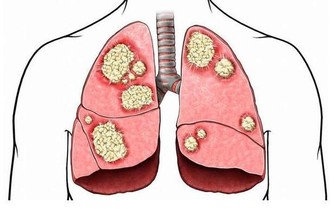

另外由於黃秋葵富含有鋅和硒等微量元素,能增強人體防癌抗癌。